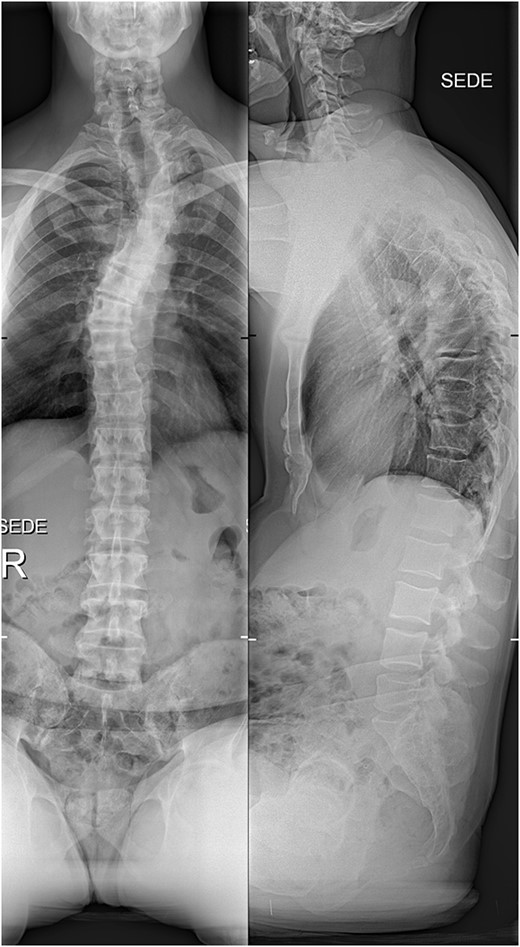

The imaging studies revealed thoracic kyphoscoliosis (with a kyphotic curve of 50°, left upper-thoracic curve of 40° and right lower-thoracic curve of 25°) and significant stenosis of the thoracic part of the spinal canal (particularly at levels Th6, Th9 and Th11) due to severely ankylosed ligamentum flavum (OLF) and the concomitant degeneration of the facets (Figs 1 and 2). Imaging indicated thoracic myelopathy (Fig. 3). We performed emergent posterior wide laminectomy using an ultrasound bone scalpel, and a partial correction of the deformity by instrumented spinal fusion (Th6-Th12). The surgery was performed by the senior author (N.H.).

The initial X-ray images of the thoracic spine at the time of admission to our institution. Anteroposterior view (left) and lateral view (right).